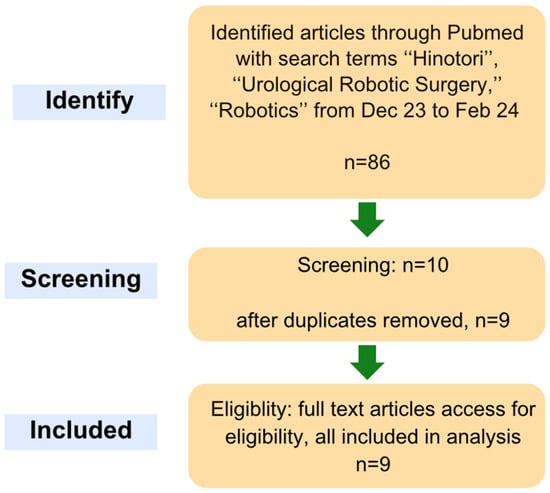

Robotic-assisted surgery has gradually established its role in uro-oncological cases that demand a high level of precision, optimising surgeon ergonomics and decreasing fatigue whilst maintaining optimal clinical outcomes. With the novel Hinotori surgical robot (Medicaroid Corporation (Kobe, Hyogo, Japan)) launched in Japan back in 2019, it has now demonstrated its use case across various clinical series of different surgeries. We sought to narratively synthesise the initial feasibility of the Hinotori robotic system in urology. A systematic, comprehensive literature search was conducted across various databases from September 2024 to October 2024. Relevant keywords within the scope of this study were generated for a more accurate search. After exclusion and removal of duplicates, a total of nine articles were included for review. Among the included studies, one study reported data solely on radical prostatectomy for prostate cancer, two studies reported on robotic-assisted nephroureterectomy for renal tumours, two studies reported on partial nephrectomy performed for renal masses, two studies reported on radical nephrectomy carried out for renal malignancies and one study reported on robotic-assisted adrenalectomy for adrenal cancer. Lastly, one study collectively reported on outcomes pertaining to partial nephrectomy, partial nephrectomy, vesicourethral anastomosis and pelvic lymph node dissection in a porcine model, as well as partial nephrectomy, radical prostatectomy and pelvic lymph node dissection in cadavers. The current literature supports its non-inferiority to the well-established Da Vinci system, with no major drawbacks or concerns identified when comparing parameters such as intraoperative time, estimated blood loss (EBL), perioperative events (transfusions, conversion to open surgery), length of hospital stay and major postoperative complications. Future studies involving larger cohorts and more complex surgical cases are essential to further evaluate the efficacy and safety of the Hinotori system. The new Hinotori robotic system offers unique three-dimensional features as a non-inferior robotic platform alternative that has proven clinically safe thus far in its use. Larger scale studies and randomised trials are eagerly awaited to assess and validate more holistically its clinical utility.

Figure 1